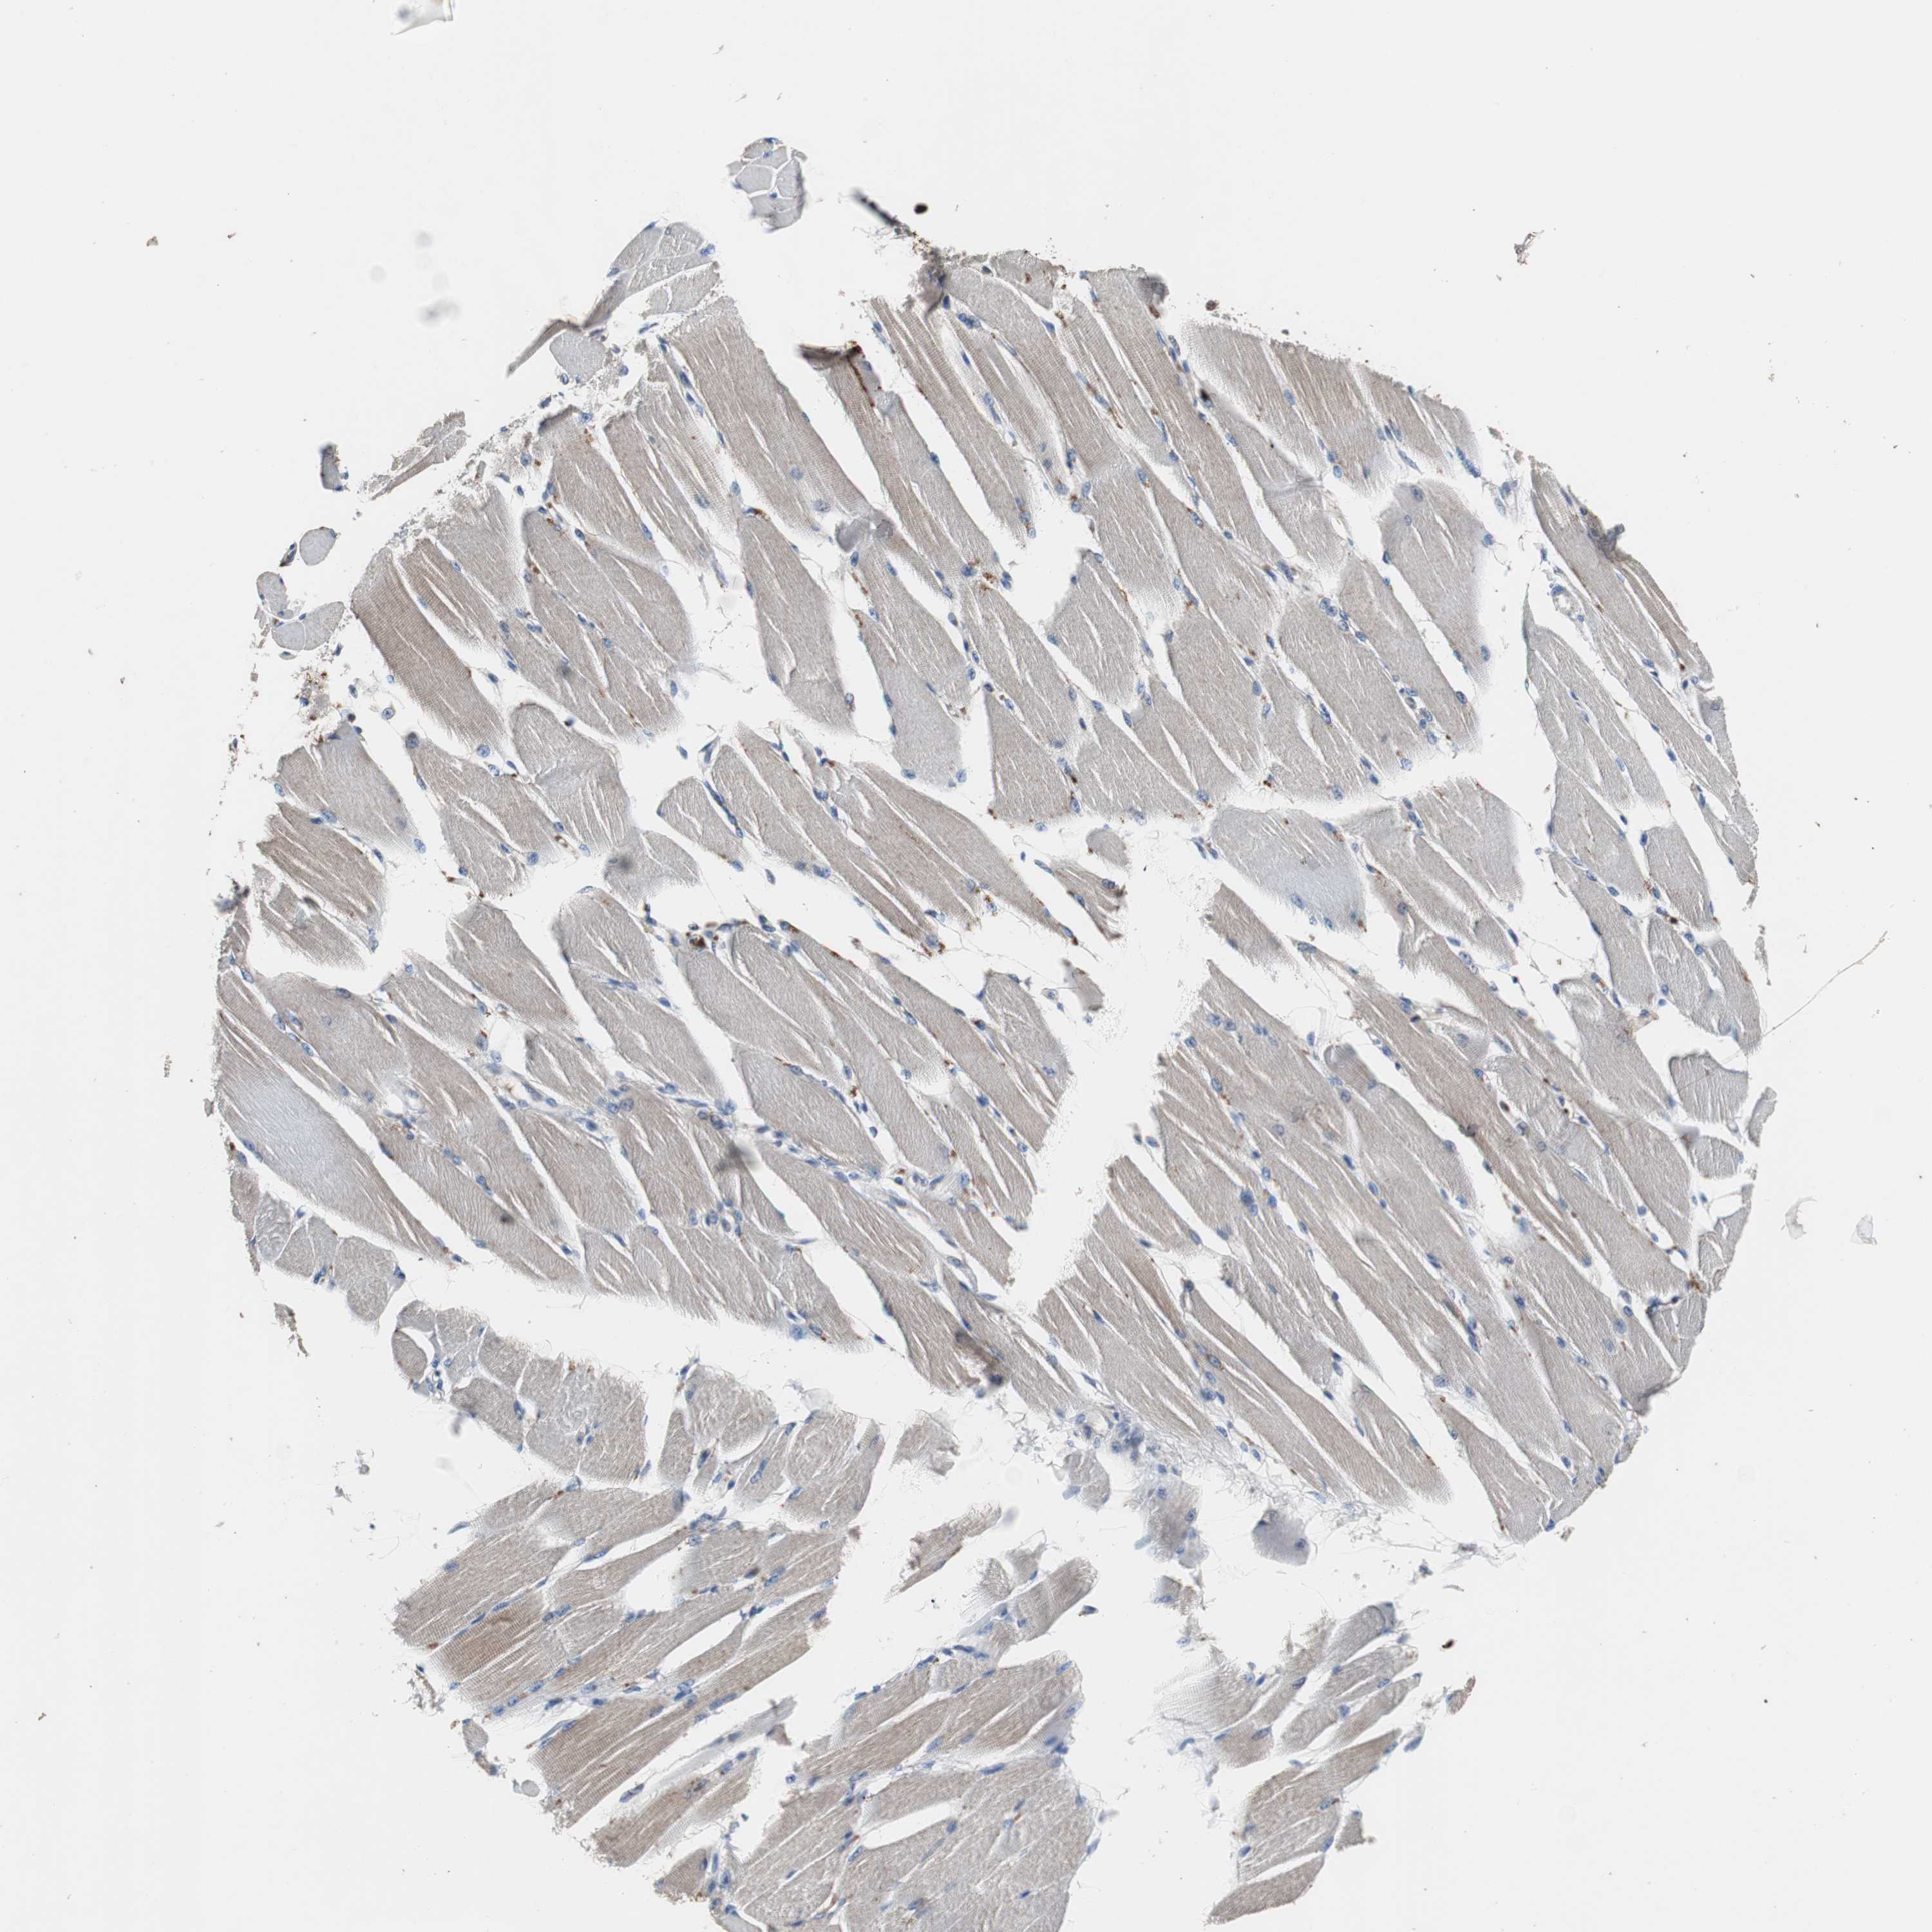

SKELETAL MUSCLE - Antibody stainingi

Antibody staining in the annotated cell types in the current human tissue is reported as not detected, low, medium, or high, based on conventional immunohistochemistry profiling in selected tissues. This score is based on the combination of the staining intensity and fraction of stained cells.

Each image is clickable and will lead to virtual microscopy that enables deeper exploration of all samples and also displays staining intensity scores, fraction scores and subcellular localization as well as patient and tissue information for each sample.

Antibody HPA007305Antibody HPA007306Antibody CAB000106

Myocytes Not detectedNot detectedNot detected